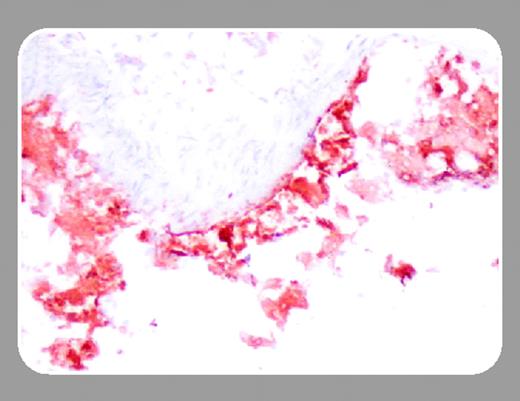

However, according to the study by Kanters and colleagues in this issue of Blood (page 934), the detrimental effect of NF-κB inhibition in atherogenesis depends on how NF-κB activity is inhibited. In this study, Kanters et al examined the effects of hematopoietic NF-κB1 (p50) deficiency in the development of atherosclerotic lesions in LDLR knockout mice. Instead of promoting the formation of larger inflammatory lesions, as was the case with IKK2 deficiency, a significant decrease in lesion size in mice with NF-κB1 deficiency, despite enhanced accumulation of T and B lymphocytes within the lesions, was observed. This could be explained, at least in part, by the observation that, in contrast to IKK2 deficiency, NF-κB1 deficiency did not lead to an alteration of the inflammatory balance in favor of a proatherogenic phenotype. Despite increased tumor necrosis factor (TNF) expression by NF-κB1–/– macrophages, other major proatherogenic molecules such as monocyte chemoattractant protein-1 (MCP-1) were down-regulated, whereas critical antiatherogenic factors such as IL-10 were significantly up-regulated. Decreased MCP-1 production and increased IL-10 expression may have contributed to limitation of plaque size despite enhanced accumulation of T cells. Another plausible mechanism leading to inhibition of lesion development in NF-κB1–deficient animals could be attributed to a potential defect in the uptake of oxidized low-density lipoprotein (oxLDL) by macrophages, as characteristic foam cells were absent in NF-κB1–/– lesions and both scavenger receptor class A (SR-A) expression and uptake of oxLDL were significantly reduced in NF-κB1–/– macrophages upon ex vivo stimulation with lipopolysaccharide (LPS). Whether this in vitro effect, observed following LPS stimulation, is relevant to the in vivo situation remains to be determined.